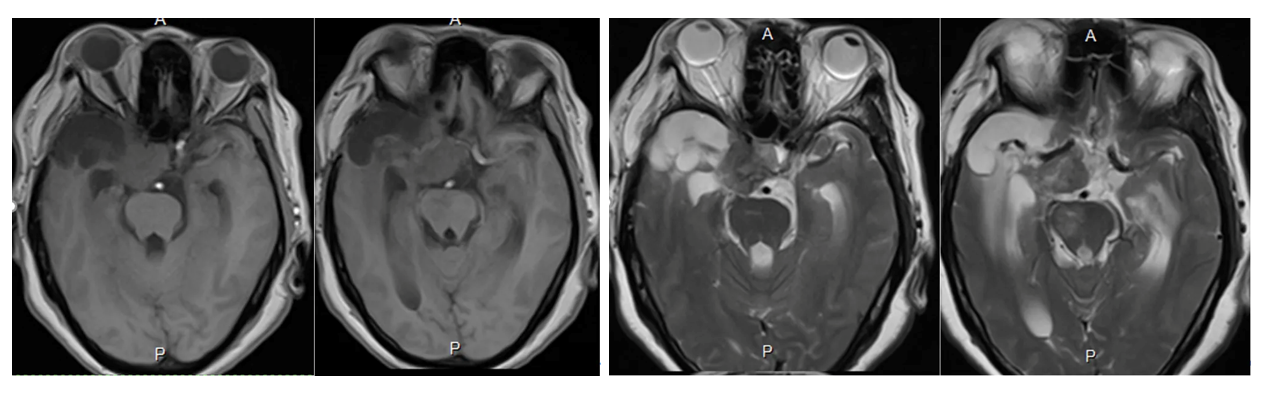

Cranial MRI enhanced

1. MRI T1 and T2 images showed a tumor in the left saddle region with long T1 and short T2 signals. The tumor was solid and encircled the internal carotid artery and branch vessels.

2. Enhanced axial and coronal-sagittal views showed that the tumor was unevenly enhanced, which was located in the saddle region, invaded the right cavernous sinus, and encircled the internal carotid artery and its branches and perforating vessels.